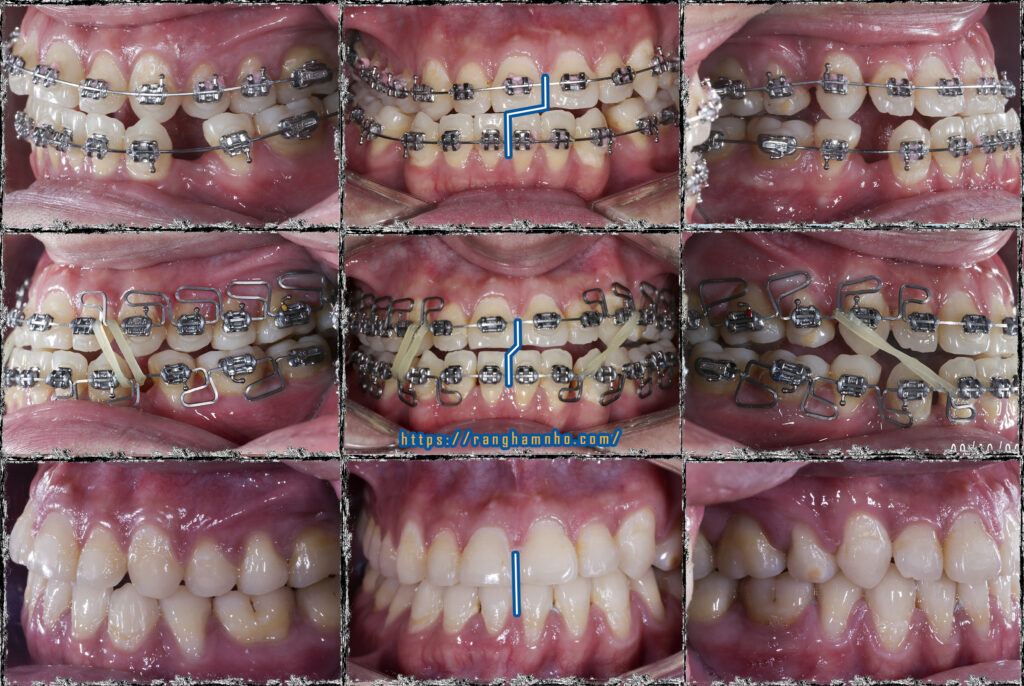

Tình hình khi gặp gỡ: còn nhiều khoảng nhổ răng, khớp cắn ngược răng cửa, cắn chéo nhóm răng hàm cung 1. Đường giữa hàm dưới lệch nguyên 1 răng cửa. Mặt thẳng lệch rất rõ, cằm đưa hẳn sang bên phải.

Xử lí: Đóng khoảng hàm dưới đến mức vừa phải để giải quyết cắn ngược răng cửa. Bẻ MEAW trên TMA 17×25 định vị lại vị trí xương hàm dưới. Sau đó chuyển lại kĩ thuật dây thẳng để kết thúc sau gần 2 năm.

Kết quả: đường giữa gần như thẳng, xương hàm dưới định vị về vị trí bình thường. Khuôn mặt cải thiện khá so với trước điều trị nhưng không thể hoàn hảo do căn nguyên sai lệch kết hợp đến từ sai lệch xương ![]()